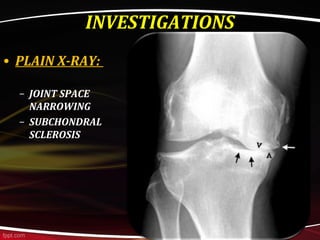

INVESTIGATIONS

• PLAIN X-RAY:

– JOINT SPACE

NARROWING

– SUBCHONDRAL

SCLEROSIS

MARGINAL OSTEOPHYTES

SUBCHONDRAL CYST

INVESTIGATIONS • PLAIN X-RAY: –JOINT SPACE NARROWING – SUBCHONDRAL SCLEROSIS